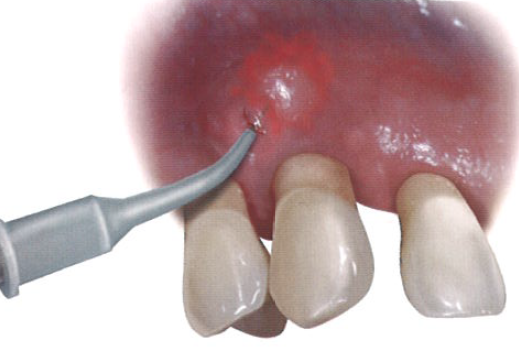

临床医师将大量具有致病性的病原菌的生物膜去除,从而阻断了由菌斑诱导的牙周炎症的复发。除了让患者在家中遵循更有效的清洁程序外,还建议使用半导体激光(图2)。

口腔激光怎么治疗“难治性”牙周炎的激光辅助治疗_https://www.jmylbn.com_新闻资讯_第4张

图2  使用半导体激光处理牙周

使用该半导体激光的目的是杀菌,并与常规的牙周非手术刮治相结合。在4个月后的随访复诊中,用轻柔的力量进行探诊,探诊深度稳定在大约5 mm,无探诊出血。